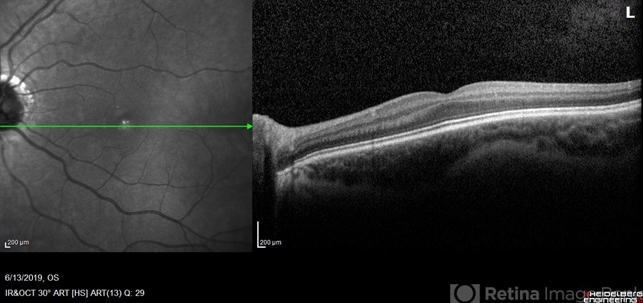

- optical coherence tomography (OCT), congenital stationary night blindness (CSNB), infrared image

- OCT/infrared image showing myopic fundus with normal retinal structure in patient with CACNA1F associated X-linked CSNB (OS).